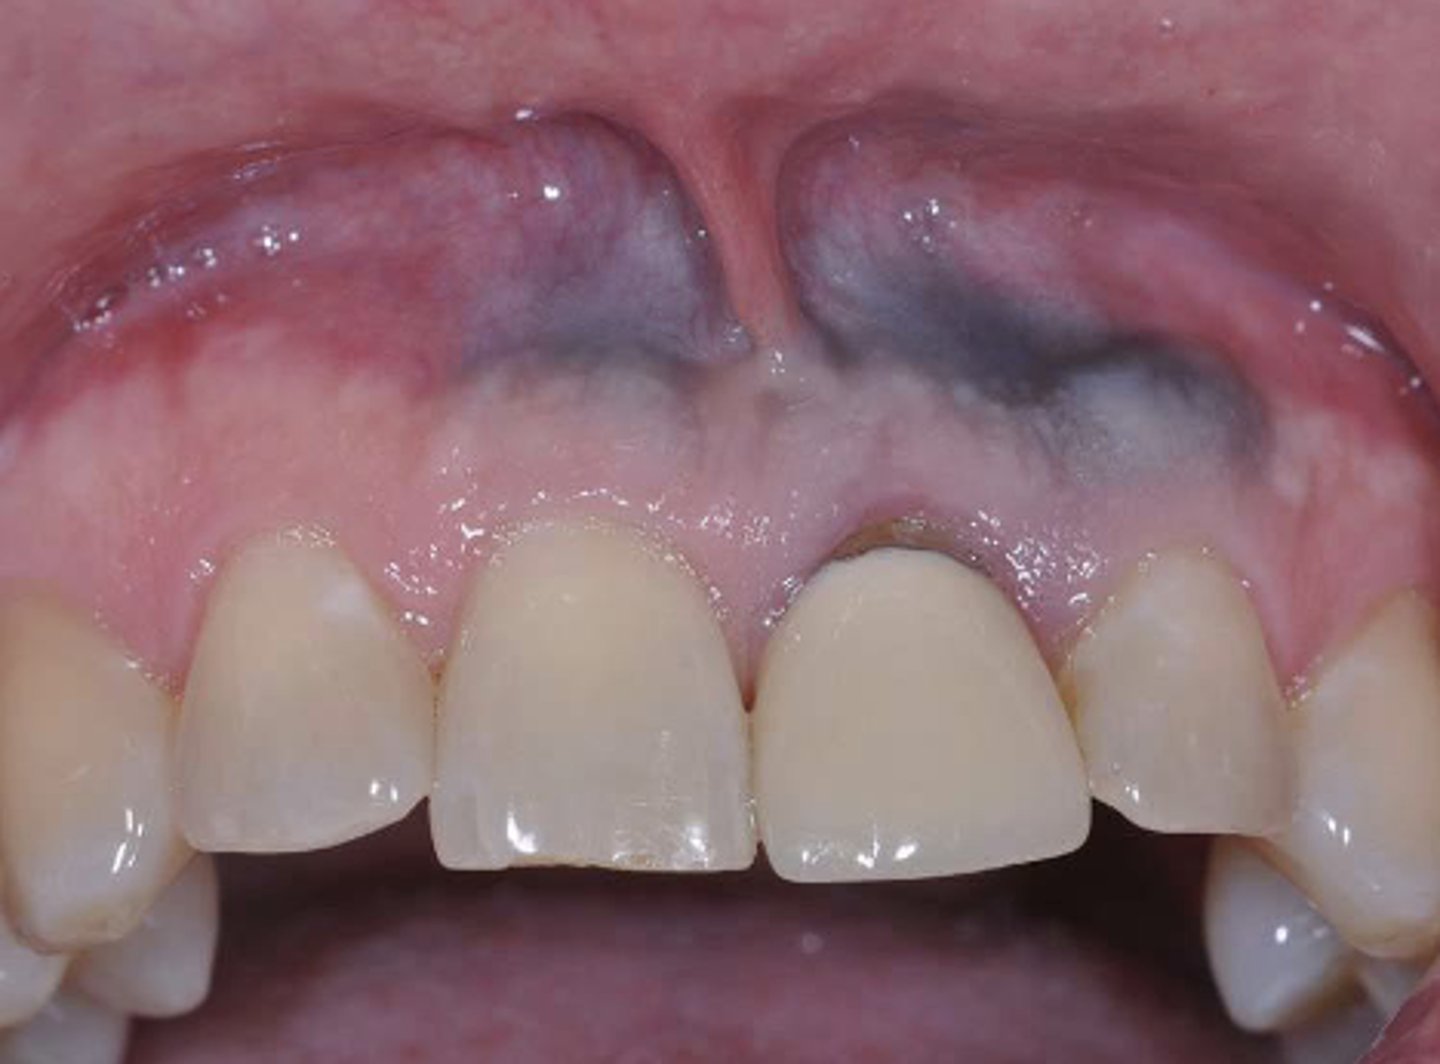

What type of pigmented lesion?

amalgam tattoo

These are clinical features of what?

- Asymptomatic, localized

- Blue-gray macule

- Localized around areas with amalgam restorations

amalgam tattoos

What is the most common location of amalgam tattoos?

gingiva/alveolar ridge mucosa (50%, then buccal mucosa, then floor of mouth)